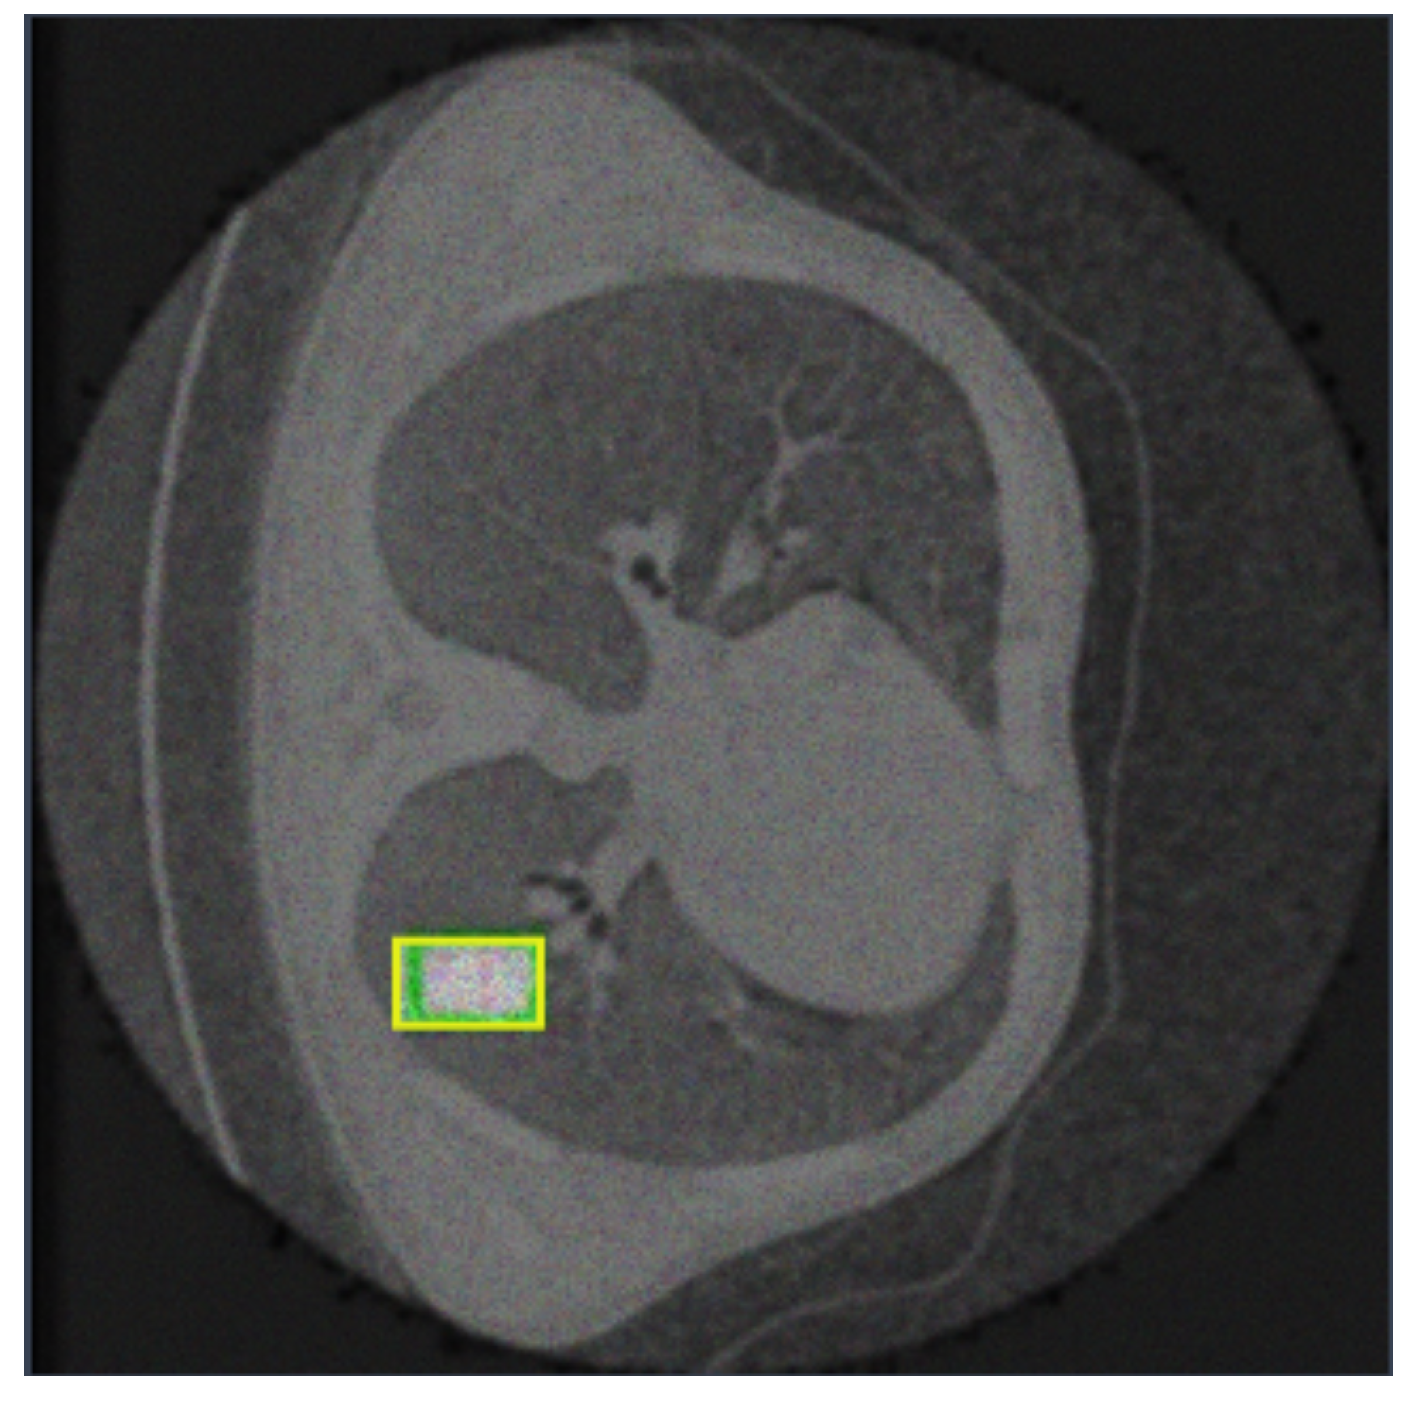

4. Experimental Analysis